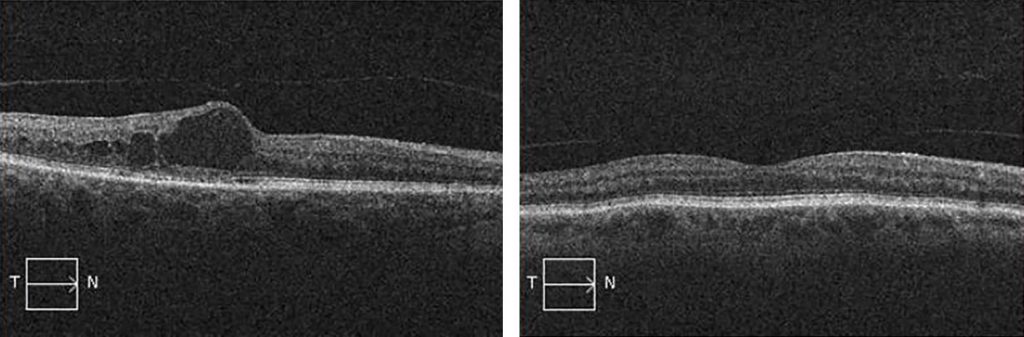

OCT image of diabetic macular edema (LEFT image). Note the large cystic structure filled with fluid (represented by the dark void) within the retinal tissue in the center of the image, which represents swelling at the fovea. Contrast this with a normal appearing retina (RIGHT image), where the tissue is uniformly thin without swelling at the fovea.